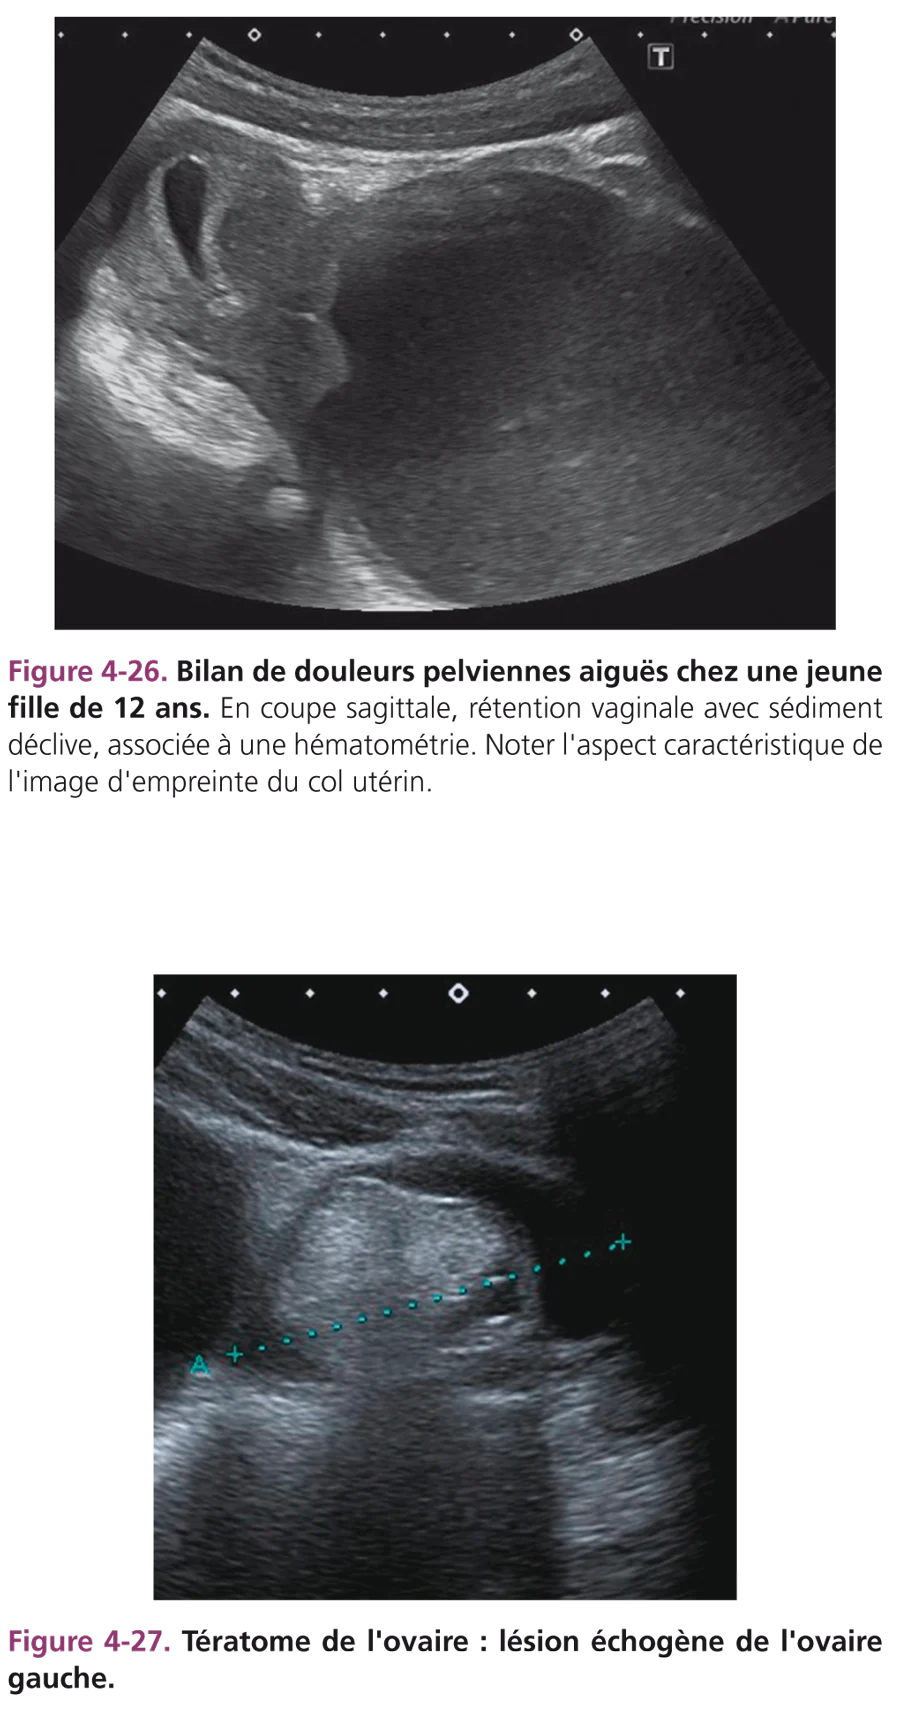

Hématocolpos

Révélé par une aménorrhée primaire et des douleurs pelviennes, son aspect échographique de rétention vaginale plus ou moins liquidienne est caractéristique (fig. 4-26). L’imperforation hyménéale est classique. Plus rarement, il s’agit d’un diaphragme ou d’une atrésie, notamment dans la forme unilatérale sur duplicité (association avec une agénésie rénale homolatérale).